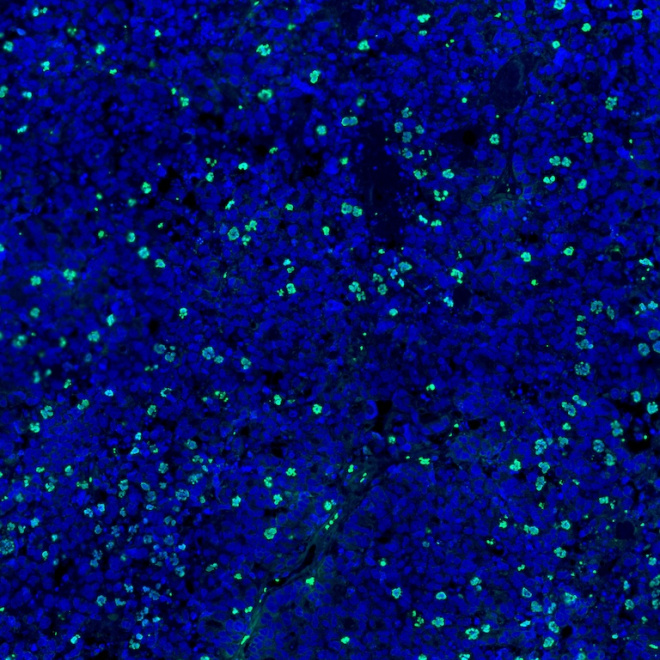

Koch Institute researchers develop new strategies to pinpoint cancer’s vulnerabilities and overcome resistance. Explore selected projects through the images below.